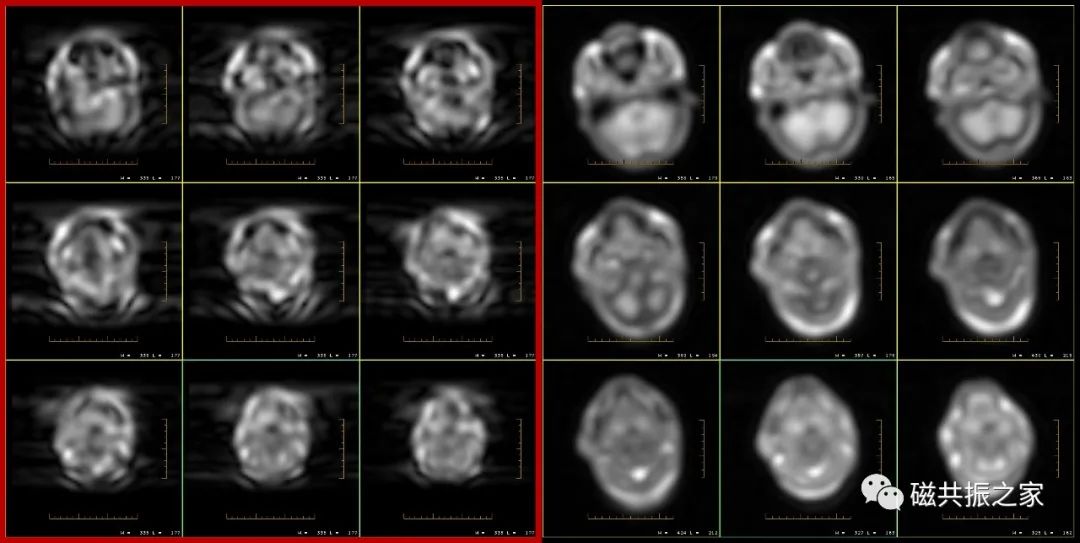

你没有看错,这的确是由于运动导致的伪影。但不是在扫描该序列时患者运动导致的伪影,而是在扫描该序列之前的校准序列时患者运动导致的伪影。两组校准序列图像如下图。

虽然校准序列的清晰度很差,但仔细观察还是能够发现其异常,如左侧第一组校准序列(红框内)出现了明显的运动伪影,右侧是正常的校准序列。遇到这种情况只有再重新扫描一次校准序列。

当使用特殊的重建技术(如内插)、K空间填充、极性梯度(如对称性梯度)等时,由于运动导致明显的失相位,造成该种运动伪影。